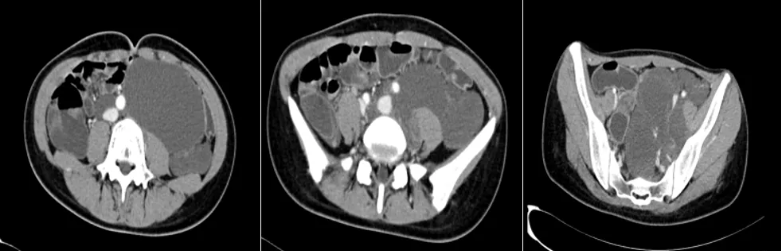

图2:结合2012.06.22日片“盆腔脉管瘤术后"改变。腹膜后腹主动脉及下腔静脉旁至盆腔左侧壁可见不规则密度增浓影,密度不均、其内部分密度稍高并,CT值约23-39HU,并可见少许小钙化,部分边缘稍模糊,较大范围约为12.7cm×7.5cm×16.4cm,增强扫描部分轻微强化,部分强化不明显,邻近子宫、肠管、膀胱、血管部分向右移位,病灶与左侧腰大肌、左侧输尿管及左侧附件区分界欠清,相应部分输尿管变窄、部分显示不清,左肾孟盏轻度增宽;病灶周围及左侧腹股沟区见多发小及轻度增大淋巴结影,较大者位于右侧腹膜后(SE2IM55),最大径约1.5cm